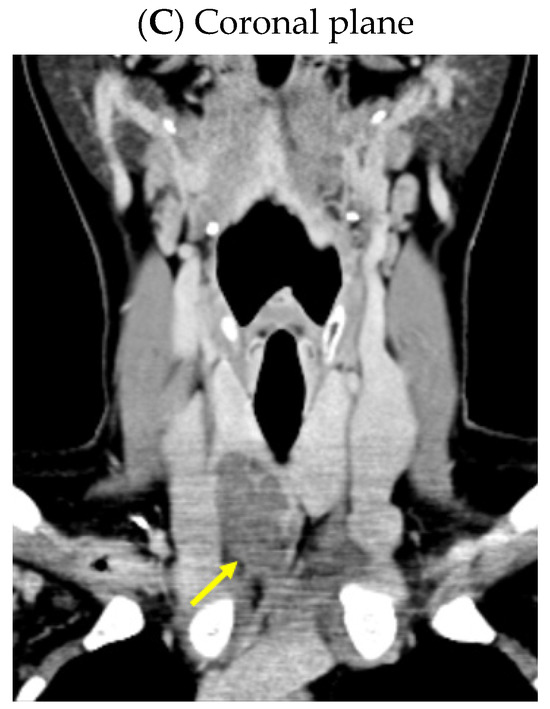

Despite recommendations, she proved poorly compliant once again, and she was re-admitted only seven months later when she suffered a spontaneous fracture at the second cervical vertebra that required immobilization with a cervical collar. Amid this novel hospitalization, the PTH levels remained high with a reduced alkaline phosphatase level (Table 4). A native spine CT revealed an odontoid fracture involving the C1 anterior arch, also confirmed with a native magnetic resonance imaging (MRI) evaluation. Moreover, other left intramaxillary bone lesions were discovered. In this context, the examinations were extended to the level of the skeleton, and the head-thorax-abdomen-pelvis CT scan with intravenous contrast revealed multiple lesions located at different levels, such as the skull (of 3.5 by 3.8 cm), sternum (of 2.9 cm), sacrum (of 4 by 5.5 cm), and pelvis (of 6.5 by 5.5 cm) (Figure 12).

Figure 12.

Brown tumors in an adult lady with poorly controlled renal hyperparathyroidism. (A) Native craniocerebral magnetic resonance imagery (the lesions are highlighted as well as their largest diameter). (B) Intravenous contrast computed tomography showing the mentioned lesions (yellow arrow) at the level of the skull (left) and spine (right).